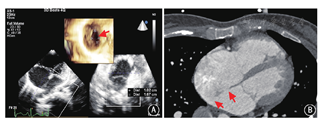

以三维超声心动图及心脏CT检查采集更详细的影像学资料(图2),运用计算机软件(Mimics Innovation Suite 19,比利时Materialise公司)合成图像并进行三维重建,选用软质硅胶材料,利用3D打印机制作心脏模型。